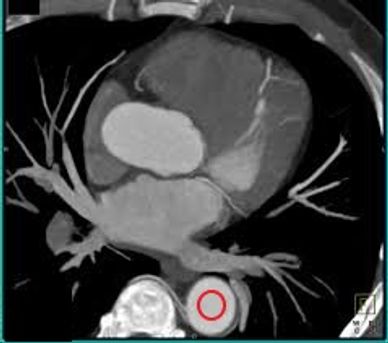

PLAN YOUR BOLUS TRACKER/SMART PREP/ROI JUST BELOW THE CARINA

SET THE ROI IN THE DESCENDING AORTA. SCAN SHOULD BE SET TO TRIGGER WHEN THE AORTA REACHES 160HU.